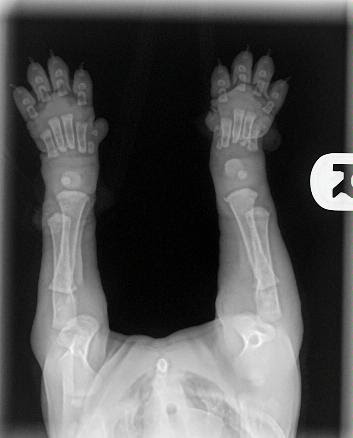

When you get your puppy, please keep these images in mind.

As you can see their bones are not even touching yet. Puppies are so cute when they jump around with their floppy little paws and wobbly legs because their joints are made up of tendons, muscle, and ligaments with skin covering. There is no socket yet and nothing fits tightly.

A bit of back-story: This is a baby puppy who had a knock to his elbow and wasn’t using it properly, so he was taken to the vet. There is nothing wrong in these x-rays, thankfully it is a soft tissue injury and he is expected to be fine.